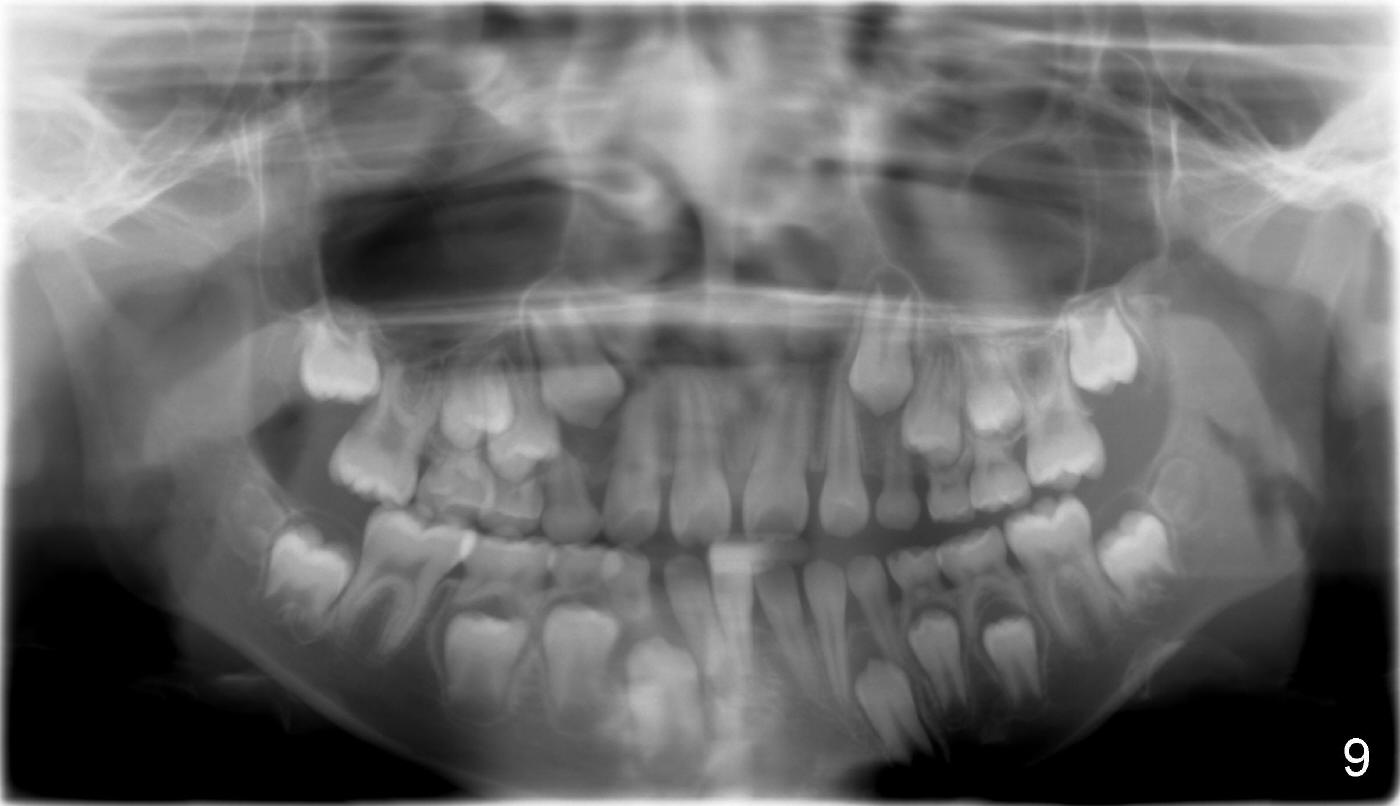

It appears that the chin deviates to the left (Fig.1). The lower dental midline also deviates (Fig.2,4). Profile shows possible bimaxillary protrusion (Fig.3). There is cross bite (deep overjet?) on the right side of the first permanent molars (Fig.5 mirror image), whereas the left posteriors apparently present edge-to-edge occlusion (Fig.6). Fig.7,8 are mirror views of the upper and lower arches, respectively. Panoramic X-ray demonstrates elongation of the right condyle (Fig.9). The right ramus appears to be longer than the left.